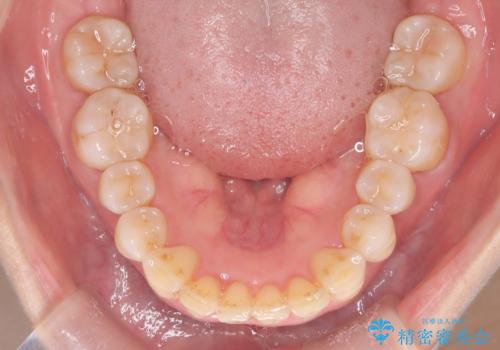

- 前歯が出ていることを主訴に来院されました。

インビザラインにて臼歯部の遠心移動及びIPRを行なっています。

叢生量が多いケースでしたが、綺麗な歯並びとなり患者様にも満足していただきました。

非抜歯矯正のため口元の変化はありません。